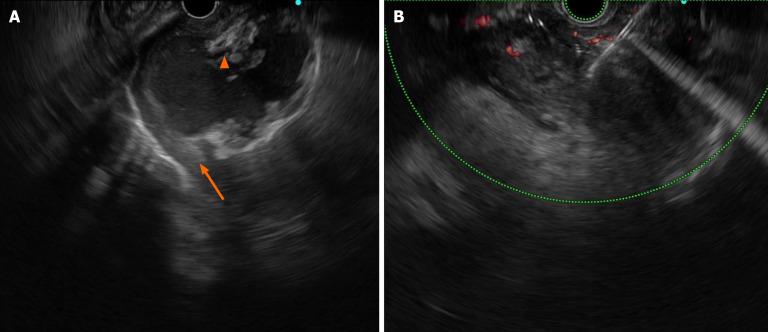

We report the case of a 43-year-old man who was admitted to the hospital with severe intake reduction due to early satiety 2 wk after treatment for acute pancreatitis; conservative treatment was ineffective, and a pancreatic pseudocyst was suspected on contrast-enhanced computed tomography (CT). Endoscopic ultrasonography (EUS) suggested hyperechoic necrotic tissue within the cyst cavity. The wall was not completely mature, and the culture of the puncture fluid was positive for A-haemolytic Streptococcus. Thus, the final diagnosis of ANC infection was made. The necrotic collection was not walled off and contained many solid components; therefore, the patient underwent EUS-guided aspiration and lavage. Two weeks after the collection was completely encapsulated, pancreatic duct stent drainage endoscopic retrograde cholangiopancreatography (ERCP) was performed, and the patient was subsequently successfully discharged. On repeat CT, the pancreatic cysts had almost disappeared during the 6-month follow-up period after surgery.

我们报告一例43岁男性患者,在急性胰腺炎治疗2周后因早饱导致严重进食减少入院;保守治疗无效,对比增强计算机断层扫描(CT)怀疑有胰腺假性囊肿。内镜超声检查(EUS)提示囊肿腔内有高回声坏死组织。囊壁未完全成熟,穿刺液培养A溶血性链球菌阳性。因此,最终诊断为ANC感染。坏死性积液未形成包裹且含有许多实性成分;因此,患者接受了EUS引导下的抽吸和灌洗。在积液完全包裹两周后,进行了胰管支架引流及内镜逆行胰胆管造影(ERCP),患者随后成功出院。术后6个月随访期间复查CT显示胰腺囊肿几乎消失。